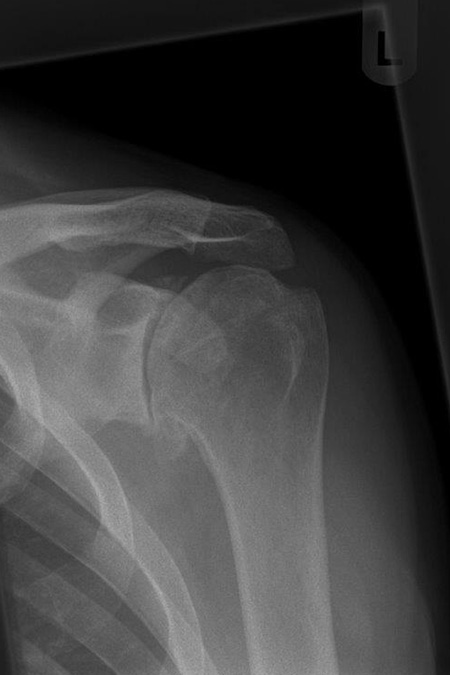

78-jährige Frau mit deutlicher Arthrose des Schultergelenks bei intakter Rotatorenmanschette – in der CT-Untersuchung keine wesentliche Dezentrierung des Gelenkes. Es wurde eine anatomische Schulterprothese mit kurzem Schaft Mitte 2019 eingesetzt mit gutem Ergebnis und Alltagstauglichkeit.

Deutliche Arthrose des Schultergelenkes mit intakter Sehnenführung. Einsetzen einer Kurzschaftendoprothese 2020 und nachfolgende Rehabilitation über 3 Monate. Sehr alltagstaugliches Ergebnis ohne Schmerzen.

Omarthrose im Röntgenbild vor der OP